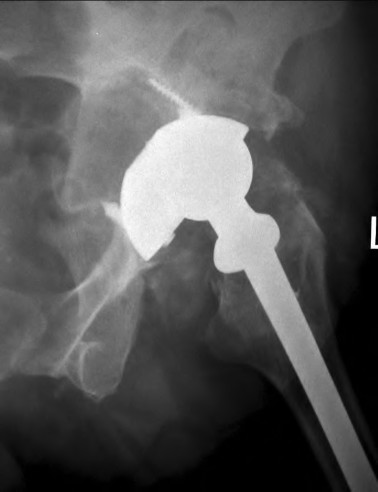

An 82-year-old woman falls and sustains the fracture shown in figure A. She denies any history of dislocation or prodromal pain prior to her fall. What is the most appropriate treatment?

The radiograph demonstrates a periprosthetic femur fracture extending to the tip of the stem. The long spiral fracture is consistent with a loose implant. The bone stock is sufficient. Therefore, this fracture pattern would classify as a B2 using the Vancouver classification system. The Vancouver classification for periprosthetic femoral fractures is simple yet incorporates all the pertinent factors such a location, stem fixation, and bone stock. Type A is a trochanteric fracture- lesser or greater. These can be treated non-operatively usually and ORIF if symptomatic. Type B fractures are around or just below the stem and are subdivided into three types. Type B1 is a fracture with a well fixed stem.

The treatment is cable plating or allograft struts or a combination of the two. Type B2 is a fracture with a loose stem with good bone stock. The treatment is a cementless porous coated long stem atleast two diameter length past the

fracture site. Type B3 is a fracture with a loose stem and comminution. For younger patients, use cementless porous coated long stems with allograft struts. For older patients, consider a tumor prosthesis. Cement fixation is sometimes necessary Type C is a fracture well below the stem tip. These can be treated independently of the prosthesis.

Springer et al showed optimal outcomes with revision involving long extensively-coated femoral stems for Vancouver B fractures.

Masri et al review the classification and treatment of periprosthetic femur fractures.